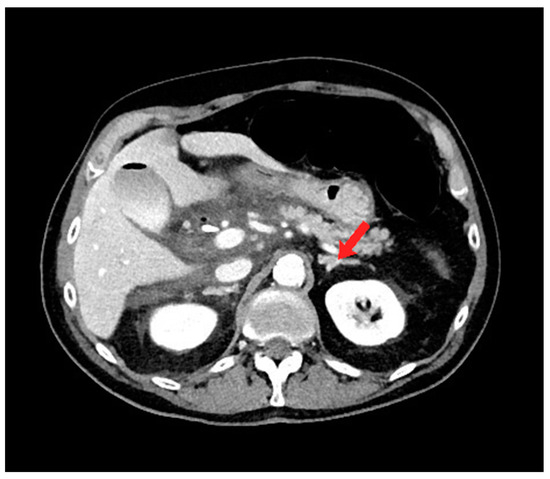

Figure 1. Axial computed tomography (CT) image shows moderate free fluid adjacent to the extrahepatic biliary system, pancreatic head, and proximal duodenum. Note the normal appearance of the left adrenal gland (red arrow).

During the CT-guided drainage, after the needle punctured the collection and a wire was placed, the patient developed sudden onset left back pain and hypertension. CT imaging revealed a spontaneous left adrenal gland hemorrhage (Figure 2b). The drainage procedure was completed by inserting a 10 French drain over the wire and formed within the central aspect of the collection; turbid fluid was aspirated (Figure 3). After the procedure, the patient was observed in the CT suite. Intravenous (IV) analgesia was administered resulting in pain relief, and serial CT imaging with IV contrast showed stability of the left adrenal hemorrhage. Intravenous antihypertensives were administered to manage the acute hypertension. The patient was subsequently hospitalized for pain and hypertension management, secondary to spontaneous adrenal hemorrhage.

Figure 3. Axial (a) and coronal (b) computed tomography (CT) imaging shows periduodenal drain placement with a 10 French catheter.